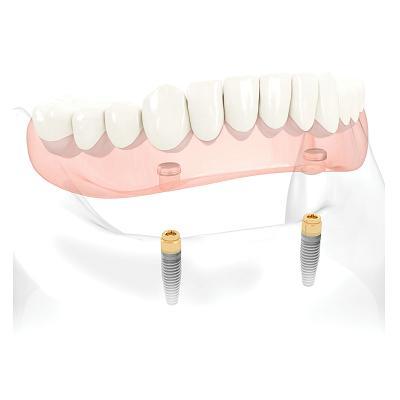

Les réhabilitations complète sur implants

La réhabilitation dentaire complète est une techniquequi vise à restaurer la fonction masticatoire et l’esthétique de l’ensemble de la bouche.

Lorsqu'il s'agit de réhabiliter complètement la dentition de manière durable, 3 techniques peuvent être envisagées :

- Prothèse complète stabilisée sur 2 implants + 2 attachements (Mâchoire du bas)

- Prothèse complète stabilisée sur 4 implants + barre (Mâchoire du haut)

- Bridge fixe transvissé sur 6 implants (mâchoire du haut) / 5 implants (mâchoire du bas)

Les avantages des réhabilitations complètes

- Retrouver une dentition complète facilite la mastication des aliments, améliore la digestion et la qualité de vie.

- Cela permet de retrouver un sourire harmonieux, booste la confiance en soi et favorise des interactions sociales positives.